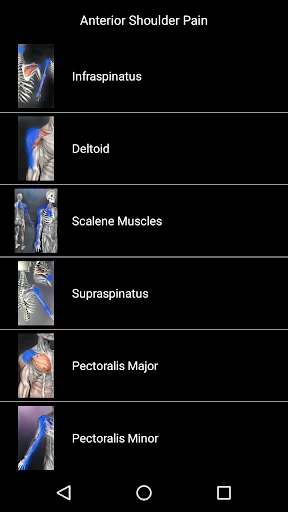

The app launches you into a detailed map of the human body, highlighting key muscle groups and their potential trigger points. This is perfect for anyone keen on learning more about their anatomy, whether you’re a seasoned athlete or just someone looking to relieve some tension. The interface is clean and intuitive, making it easy to navigate through the complex web of musculature.

What I really enjoyed about this app is the interactive element. You can tap on different muscle groups to see common trigger points, and it provides detailed descriptions of each. This isn’t just a static anatomy chart; it’s like having a mini anatomy lesson in your pocket. Plus, the app includes helpful tips on how to alleviate discomfort in these areas, which I found quite practical.

While this app is a great tool for anyone interested in muscle health, it’s especially useful for athletes, physiotherapists, and fitness enthusiasts. If you’re someone who frequently deals with muscle pain or stiffness, this could be your go-to resource. Even if you’re not an expert, the app does a great job of breaking down complex information into digestible bits.